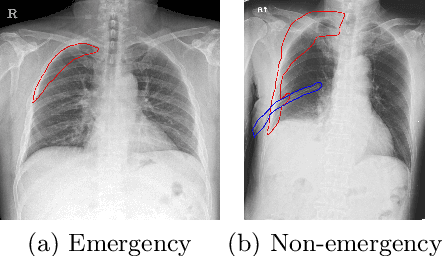

Finding diseases from an X-ray image is an important yet highly challenging task. Current methods for solving this task exploit various characteristics of the chest X-ray image, but one of the most important characteristics is still missing: the necessity of comparison between related regions in an image. In this paper, we present Attend-and-Compare Module (ACM) for capturing the difference between an object of interest and its corresponding context. We show that explicit difference modeling can be very helpful in tasks that require direct comparison between locations from afar. This module can be plugged into existing deep learning models. For evaluation, we apply our module to three chest X-ray recognition tasks and COCO object detection & segmentation tasks and observe consistent improvements across tasks. The code is available at https://github.com/mk-minchul/attend-and-compare.